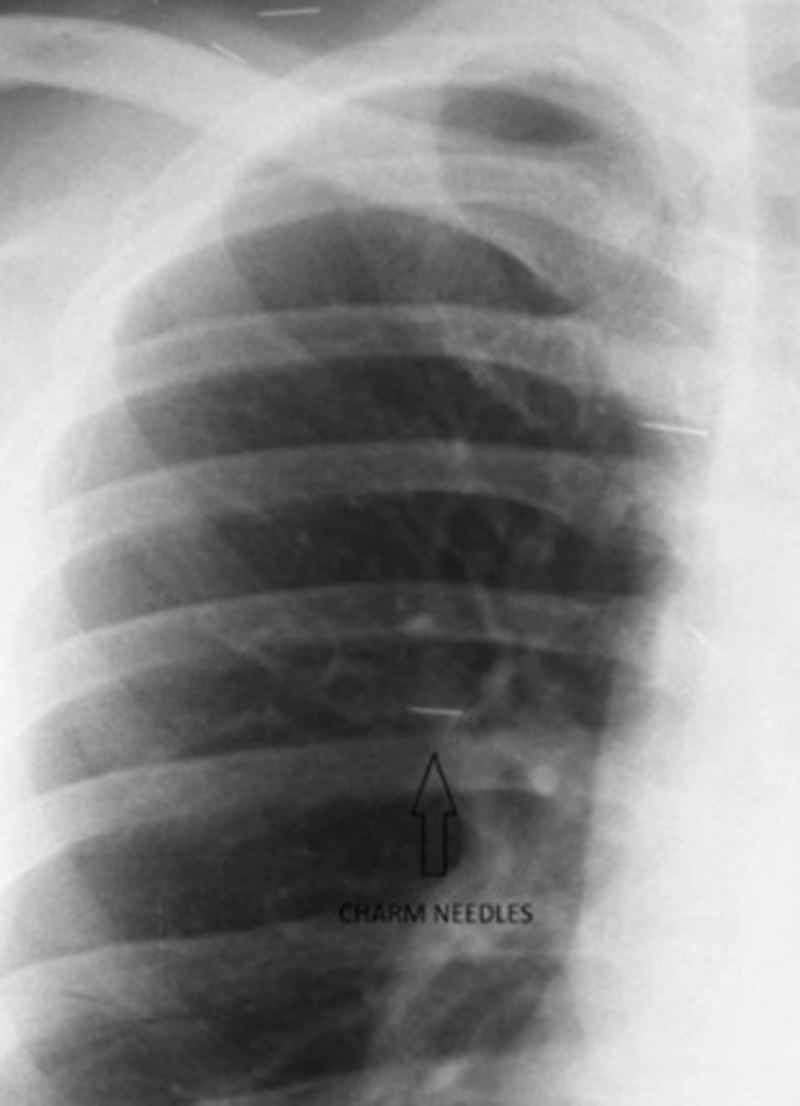

ภายหลังจากการตรวจร่างกาย ตรวจเลือด ทำซีทีสแกน และเอกซเรย์ ทางทีมแพทย์ต่างก็ประหลาดใจไม่น้อยเมื่อพบว่า มีเข็มฝังอยู่ทั่วร่างกายของเธอ กระจายอยู่ 4 ส่วน ได้แก่ บริเวณดวงตา ใบหน้า ลำคอ และหน้าอก โดยเข็มดังกล่าวนี้ เป็นเข็มบาง ๆ ทำด้วยทองหรือวัสดุโลหะอื่น ๆ เรียกกันว่า ซูสุก (Susuk) หรือเข็มเสน่ห์ ตามความเชื่อท้องถิ่นที่ได้รับอิทธิพลมาจากอินโดนีเซีย ผู้หญิงหลายคนเชื่อว่าการสอดเข็มเล็ก ๆ นี้ เข้าไปในส่วนต่าง ๆ ของร่างกายจะช่วยให้ผู้คนเกิดความลุ่มหลง ทำอะไรก็จะสำเร็จดั่งที่ใจปรารถนา